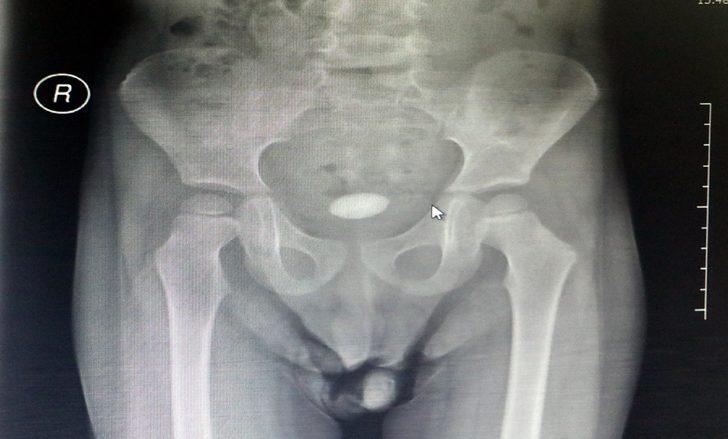

Zonguldak'ta, 3 yaşındaki U.T.'nin, karın ağrısı şikayetiyle gittiği hastanede mesanesinde tespit edilen 3 santim boyundaki taş ameliyatla alındı. Üroloji Uzmanı Dr. Okan Biçgi, bunun çocuklarda nadir görülen bir olay olduğunu belirterek, "İdrar torbasının içindeki taşı aldık. Şu anda ayağa kalktı, dolaşıyor. Şikayetleri büyük oranda azaldı" dedi.

İdrar yollarında rahatsızlık yaşayan U.T., ailesi tarafından önceki gün özel hastaneye götürüldü. Dr. Okan Biçgi'nin muayene ederek röntgenini çektiği U.T.'nin mesanesinde 3 santimetre boyunda taş olduğu tespit edildi. U.T.'nin mesanesindeki taş, dün gerçekleştirilen ameliyatla alındı. Ağrıları geçen U.T., sağlığına kavuştu. Ameliyatın ardından taşı gören U.T.'nin ailesi şaşkınlık yaşadı.

Ameliyatla ilgili bilgi veren Dr. Okan Biçgi, "3 yaşında bir erkek hastamız. Hastanemize idrar yollarıyla ilgili şikayetleriyle başvurdu. Çocuk hastalıkları uzmanımız değerlendirdi ve yaptığımız tahlillerde mesanesinde 3 santimetrelik taş olduğunu tespit ettik. Böbreklerin de değerlendirmesi ve kan analizleri yaptıktan sonra bir operasyon planladık. Bu gibi taşlarda önce enfeksiyon riskini ortadan kaldırmak ve çocuğa en az zarar verecek şekilde bu taştan kurtulmaktır amaç. Biz açık cerrahiyi tercih ettik. Bu delikanlıda yaptığımız ameliyat açık olarak idrar torbasının içindeki taşı aldık. Şu anda ayağa kalktı, dolaşıyor. Şikayetleri büyük oranda azaldı. Bir hafta kadar hastanemizde kalacak ve sonra evine göndereceğiz" dedi.